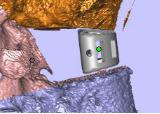

定制個性化融合器 假體置于病例模型中

需要截骨的平面 截骨導板放置位置